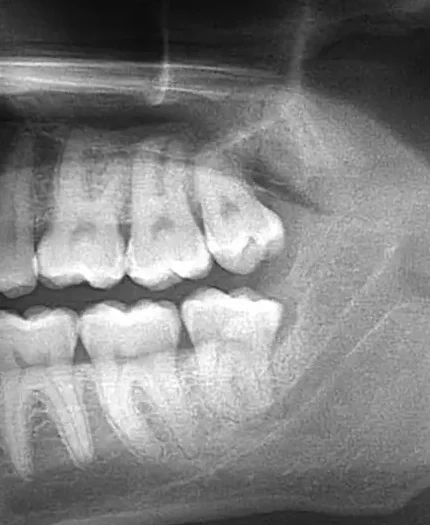

Infected Upper and lower wisdom teeth Extraction

31 year old  male patient was having gum pain around his lower wisdom tooth.  The gum was swelling due to an infected wisdom tooth as was seen on the x-rays.   An emergency dental extraction was performed.  The wisdom teeth roots were very curvy and had to be carefully extracted to avoid a tooth fracture.  Both teeth were painlessly extracted within a few minutes using local anesthesia.